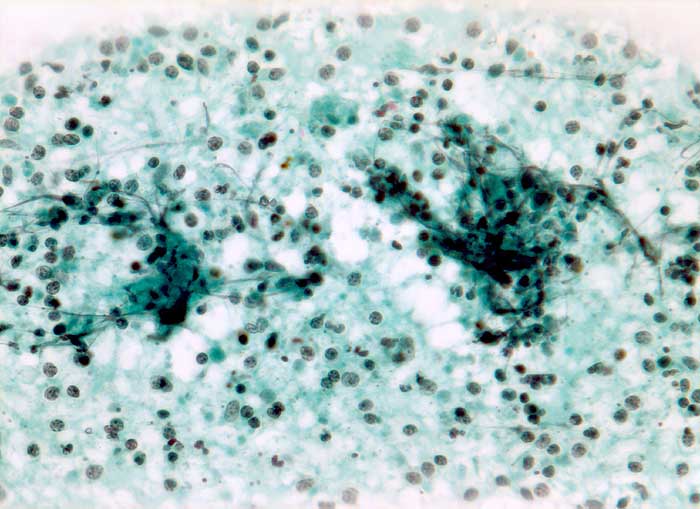

Feinnadelpunktion Lymphknoten submandibulär: Die nicht sehr zellreichen Ausstriche enthalten Detritus vermischt mit neutrophilen Granulozyten und Kerntrümmern.

Zytologische Diagnose: Ausgeprägte granulozytäre Entzündung. Keine Malignitätszeichen.